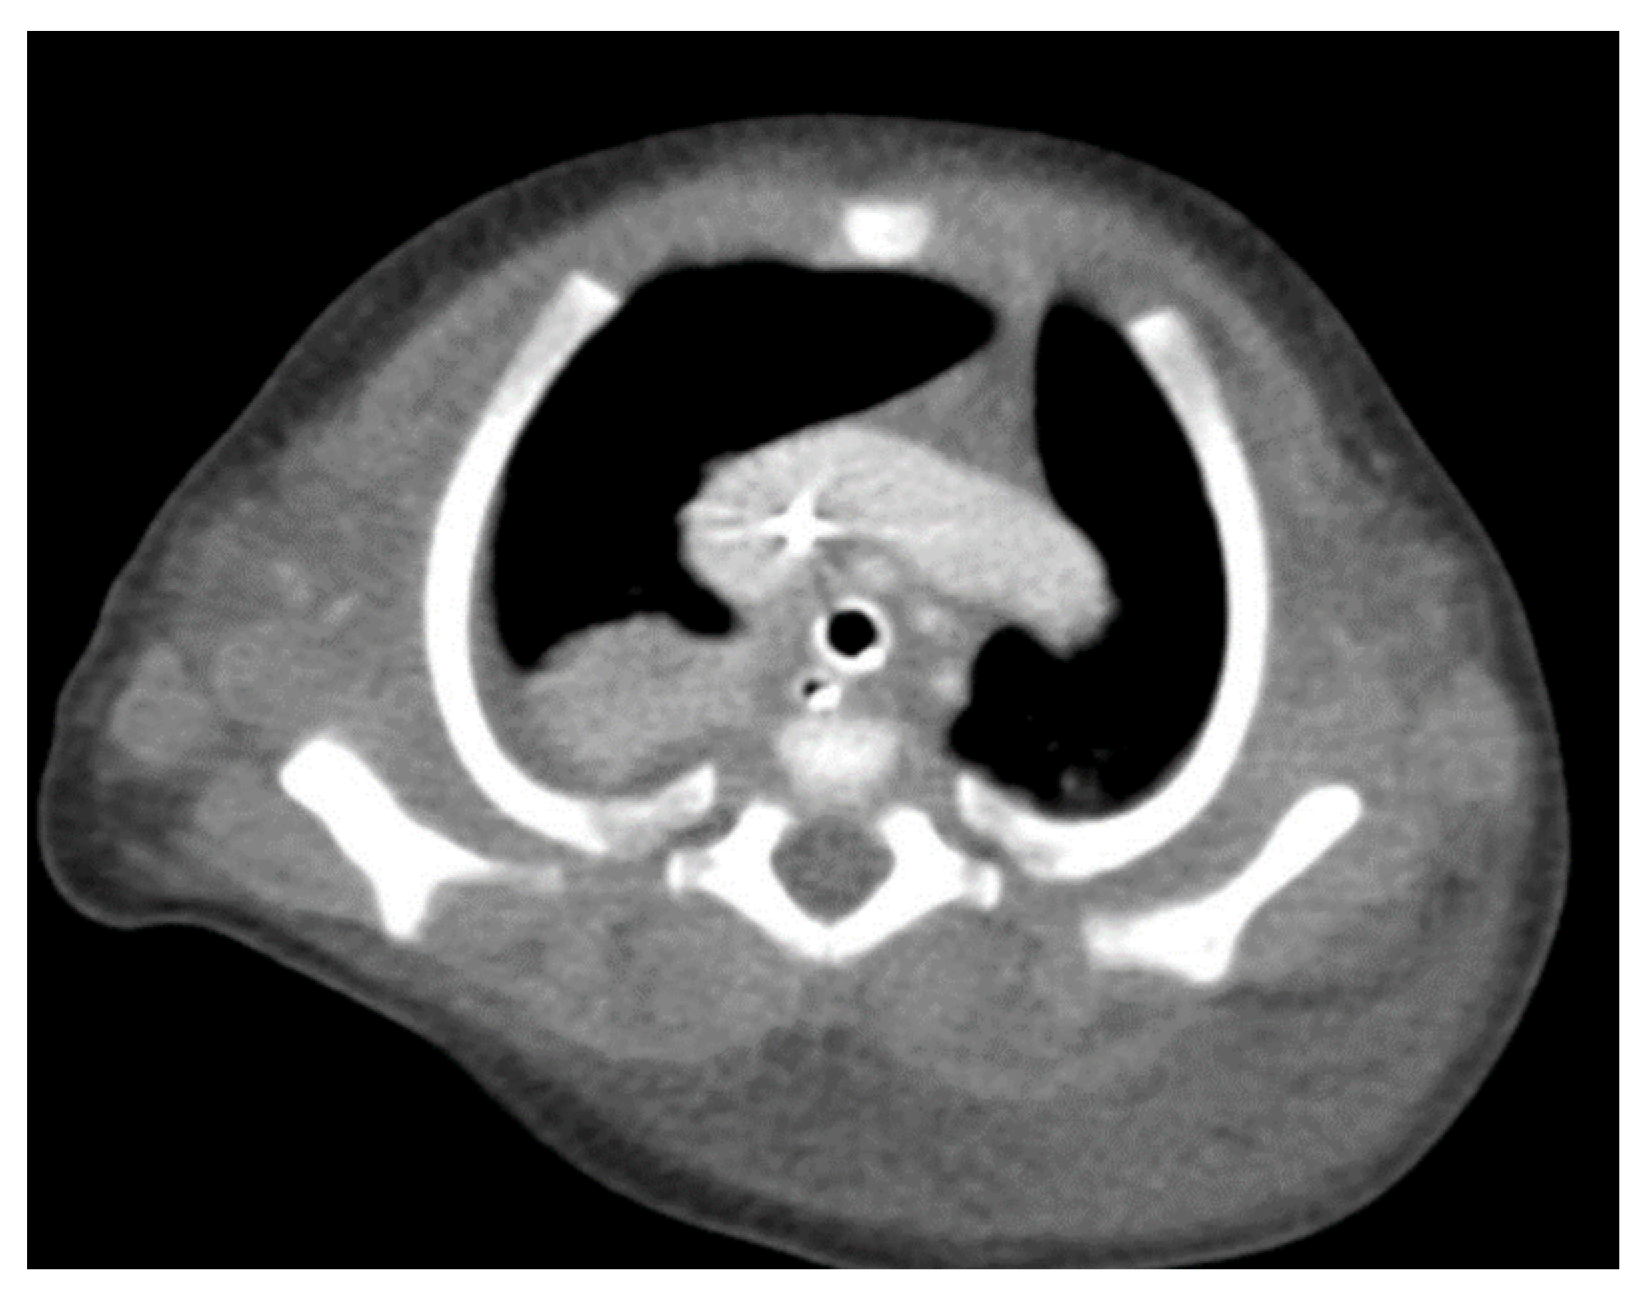

Through thoracic CT, we found SVC with a diameter of 15 mm (Figure 1), a venous collector with a 12 mm in diameter connected to the SVC and identified at the level of a plane passing through the middle of the left superior pulmonary lobe (Figure 2). The venous structure continues superiorly with the left brachiocephalic venous trunk, which was dilated up to 12 mm (Figure 3) and inferiorly with a left pulmonary vein. The pulmonary trunk appeared shorter, with a diameter of 6 mm, right pulmonary artery = 5.4 mm and left pulmonary artery = 5.6 mm (Figure 4 and Figure 5). We have identified traits of pulmonary consolidation (Figure 6).

Figure 3.

Venous brachiocephalic trunk.